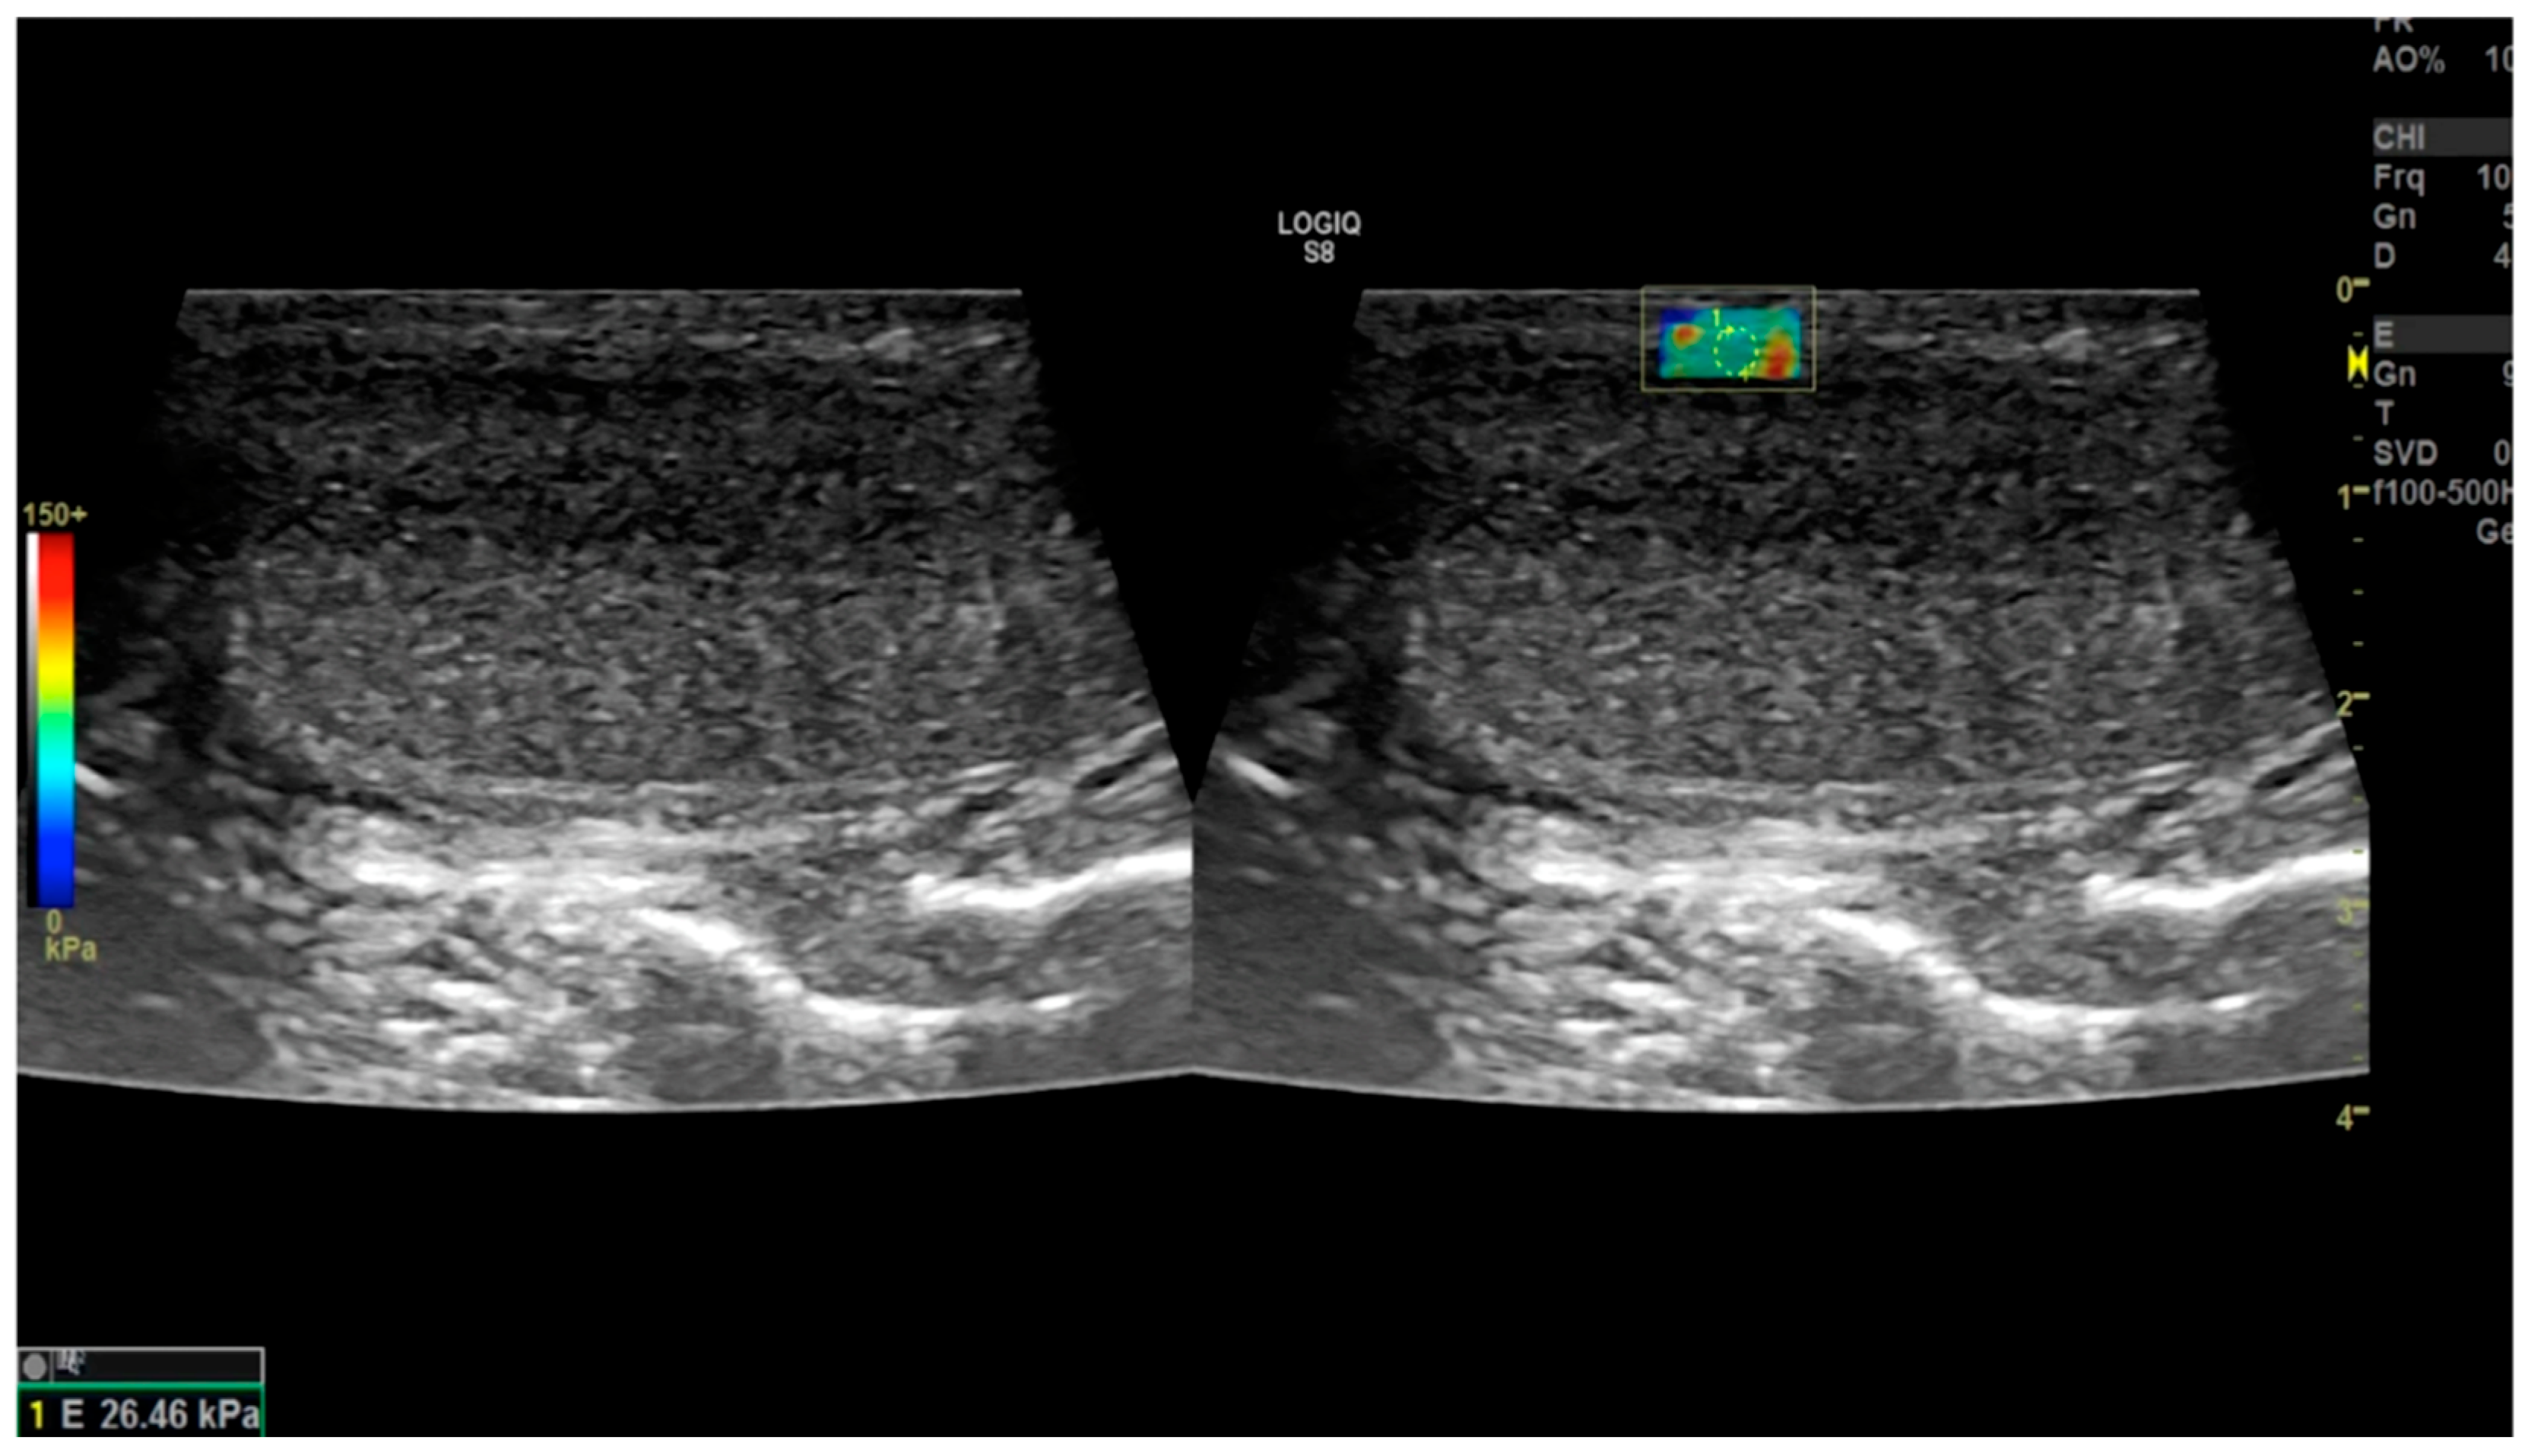

2.4.7. Trama et al. (2022) [44]

- Trama, F.; Illiano, E.; Iacono, F.; Ruffo, A.; di Lauro, G.; Aveta, A.; Crocetto, F.; Manfredi, C.; Costantini, E. Use of penile shear wave elastosonography for the diagnosis of Peyronie’s Disease: A prospective case-control study. Basic Clin. Androl. 2022, 32, 15. [Google Scholar] [CrossRef]